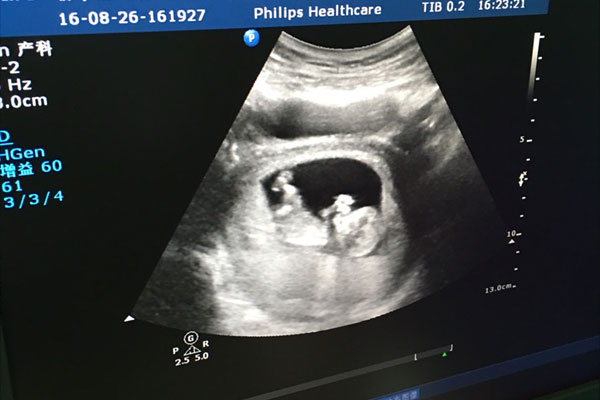

就对于nt检查,我相信大家都是知道的吧,这是孕早期非常有必要的一项检查,通过检查胎儿的颈后透明层厚薄,根据最终数值判断是否存在发育异常等存在。就对于nt检查什么时候做合适这个问题,可谓是让不少没经验的孕妈纠结了,太早怕检查不了,太晚怕错过了最佳时机,那么孕11周做nt会不会太早呢?下面就随本文一起来了解下吧。

医生介绍,一般nt检查都是建议在11周-13周+6之间做是最合适的,太早的话胎儿还是个胚胎,不能满足此时的检查标准,太晚的话则检查结果可能有出入,如有异常等情况也无法及时发现并处理,多以说在孕11周做nt也不是太早,如果胎儿宝宝孕周偏小的话,医生也不会进行检查,会让孕妇在一个星期后再来重新检查,也就是12周的时候,大家还是以自己的实际孕周为准,或者听医生建议。

一般在孕11周去nt,只要胎儿此时配合好,孕周不偏小的话都是可以很好的看到胎儿颈部透明层以及鼻骨状况的,如果nt不配合或者看不到的话医生会建议等一周再去检查,有的nt检查单子上会写着鼻骨清晰欠佳这样的字。就一般来说,孕早期做nt检查可以根据透明层厚薄筛查胎儿是否有染色体异常的情况,还可以筛查心血管异常。如果透明层增厚,建议做染色体检查。

一般情况下,透明层厚度在3mm以下都属于正常,有的医院是2.5mm以下,如果nt值处于正常的范围内,则说明胎儿发育良好,如果nt值有临界风险或者超过正常值的话,建议做一下无创DNA或者羊水穿刺,一般前者风险小一些。就一般来说,出现异常情况的几率不是很大,不管是哪一项检查,大家都保持平常心,不要有太大的心理负担和压力。